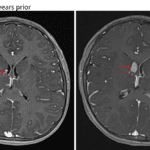

Indication: Screening MRI in patient with tuberous sclerosis

- Interval enlargement of an enhancing subependymal nodule near the right foramen of Monro measuring 1.5 x 1 cm

- Multiple additional subcentimeter enhancing subependymal nodules

- Multiple T2/FLAIR hyperintense cortical and juxtacortical lesions in the bilateral cerebral hemispheres

Subependymal giant cell astrocytoma (SEGA)